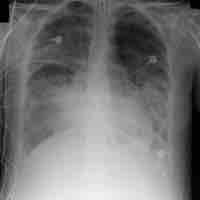

Respiratory Distress Syndrome

Acute respiratory distress syndrome (ARDS) is a serious reaction to various forms of injuries or acute infection to the lung.